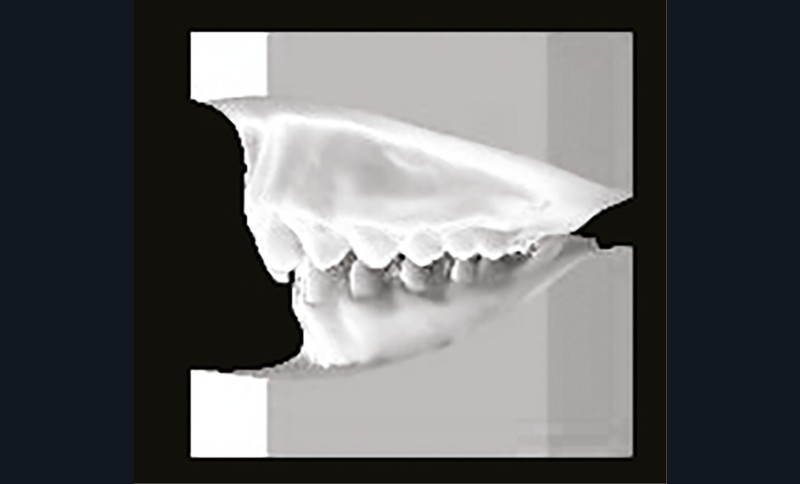

Son profil convexe s’inscrit dans un contexte de classe II squelettique par rétrognathie mandibulaire normodivergente sur un schéma de Classe II/2 avec supraclusion et encombrement modéré (fig. 1 à 7).